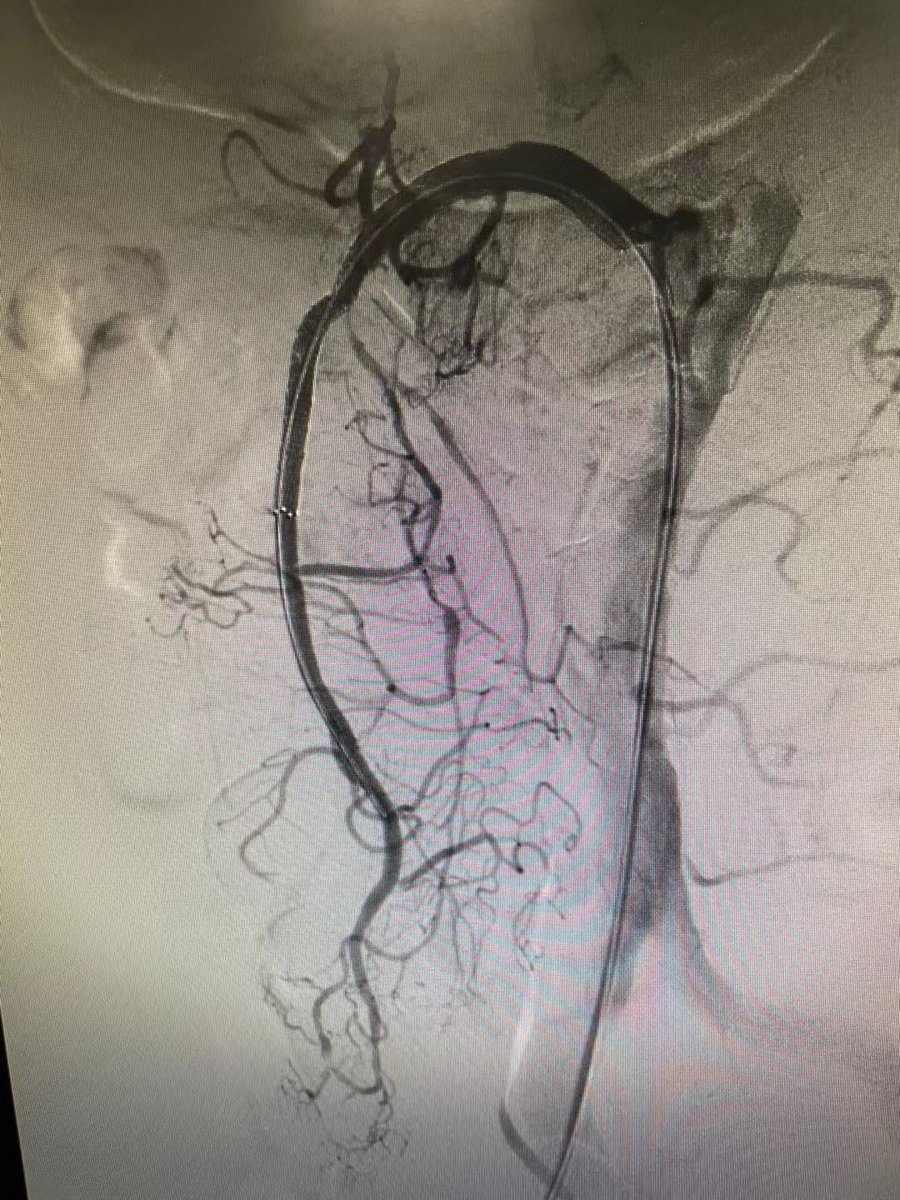

39 yo F on #OCPs. Acute Lt. LL pain n swelling, extensive #DVT, CT confirms #MayThurner #syndrome. Thrombolysis, Thrombectomy done using #AngioJet, followed by #venoplasty & stenting. #IRad is #OneStopShop! @SIRspecialists @pakIRSP @cirsesociety @rahilkassamali @drsaadrehman 1/2

Iliac occlusion crossed - felt to be acute on chronic. Angiojet pulse spray 10mg in 100ml Angiojet thrombectomy 100s Iliac thrombus cleared and underlying stenosis identified. 10mm X 8cm bare metal stent deployed. TPA infusion left for SFA and pop thrombus